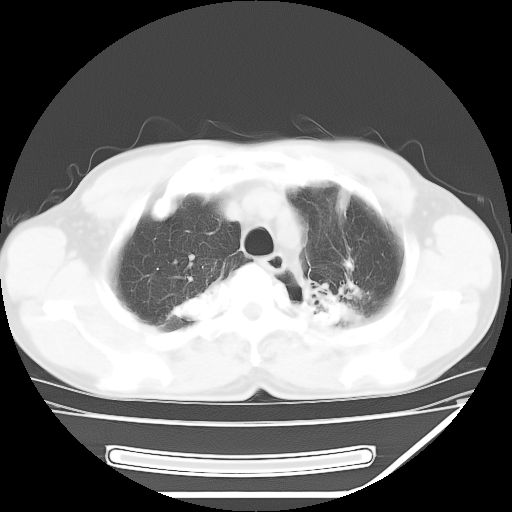

男,59岁,“结核性胸膜炎”30余年,胸部经常疼痛,多次x检查提示“肺部”炎症。腹部疼痛5日,b超提示:“肝内短管结石,余显示不清,建议进一步检查。”

两肺结核并右侧胸腔积液;脾脏、腹腔及腹膜后淋巴结结核[陈旧性];肝内胆管结石

胸部腹部都是结核(双肺。纵隔淋巴结,肝脏,脾脏,肠系膜)